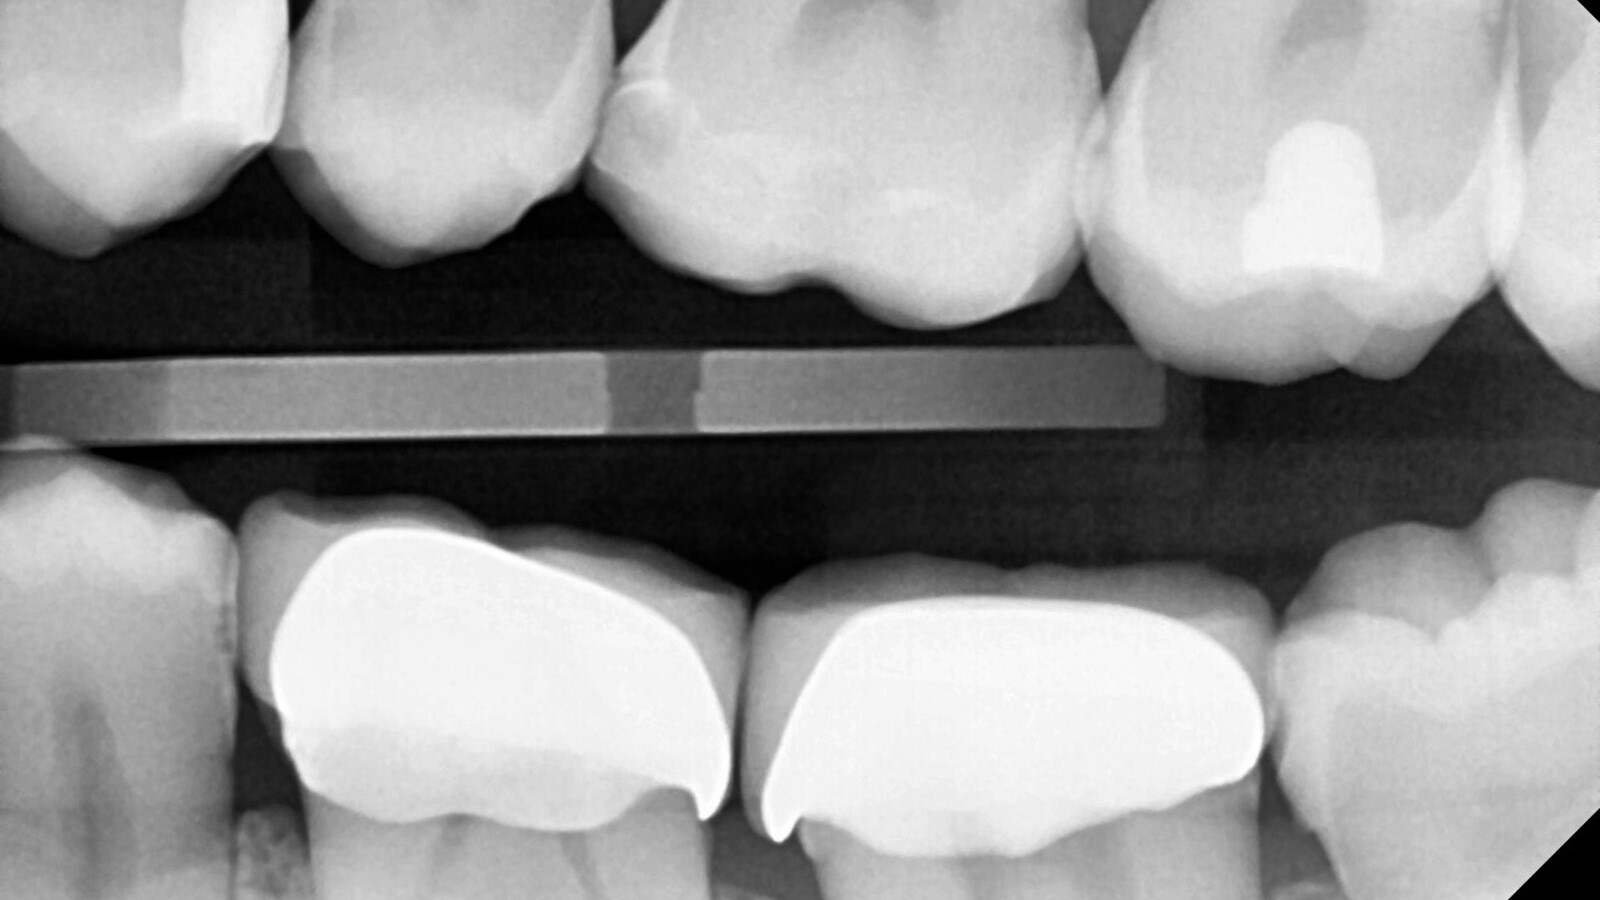

Professor Ernst identifizierte zunächst die versteckte Karies und öffnete die kariöse Läsion, um dem Patienten das Problem zu veranschaulichen (Abb. 1-2). Anschließend exkavierte er die Karies, präparierte die Kavität und setzte eine Teilmatrize ein (Abb. 3), bevor er die Kavität mit Adhäsiv versiegelte (Abb. 4). In einem einzigen Schritt füllte er die Kavität mit Venus Bulk Flow ONE (Abb. 5). Nach der Fertigstellung polierte Prof. Ernst die Restauration (Abb. 6) und fertigte ein Kontrollröntgenbild an, das ebenfalls die hervorragende Röntgenopazität von Venus Bulk Flow ONE zeigt (Abb. 7).

Venus Bulk Flow ONE ist ein vielseitig einsetzbares Komposit, das für ein breites Spektrum von Indikationen geeignet ist: Es kann für direkte Restaurationen der Klassen I, II, III und V, für Reparaturen von direkten und indirekten Restaurationen, als erste Schicht in Kavitäten der Klassen I und II, zur Schienung gelockerter Zähne und zur erweiterten Fissurenversiegelung verwendet werden. Aufgrund seiner Viskosität und seines kontrollierten Fließverhaltens eignet es sich bestens zur Schienung von gelockerten Zähnen, die durch ein Trauma oder parodontale Ereignisse entstanden sind. Darüber hinaus bietet es einen zusätzlichen Schutz für die Zahnoberfläche und ist daher eine hervorragende Option für die erweiterte Fissurenversiegelung. Venus Bulk Flow ONE ermöglicht Zahnärzten dank seiner geringen Schrumpfung, seiner hohen Biegebruchfestigkeit und seiner Abrasionsstabilität langlebige Restaurationen.